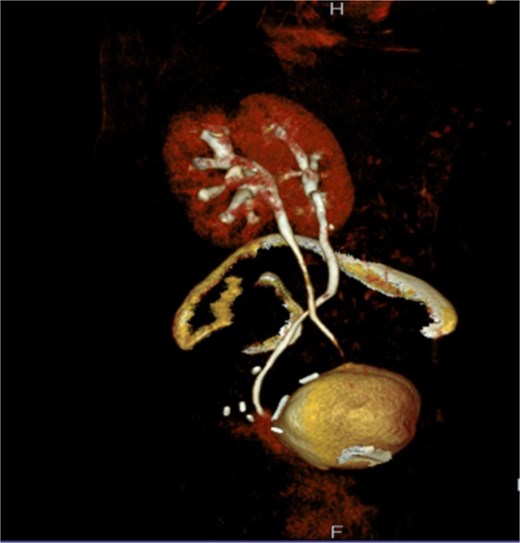

A CT nephrotomography with contrast enhancement was performed and identified an abnormal communication between the right ureter and the vagina reporting an UVF (Fig. 1). Moreover, a retrograde cystography was also performed without any findings. Due to the high suspicion of an intraoperative ureteral trauma, a conservative management was decided and a percutaneous nephrostomy was placed in the right kidney, aiming to prevent further urinary leakage from the vagina and to avoid further dilation of the kidney.

A: Diagnostic nephrotomography showing the existence of an UVF. B: CT nephrotomography showing the abnormal passage of intravenous contrast enhancement fluid from the ureter to vagina, confirming the existence of an UVF.